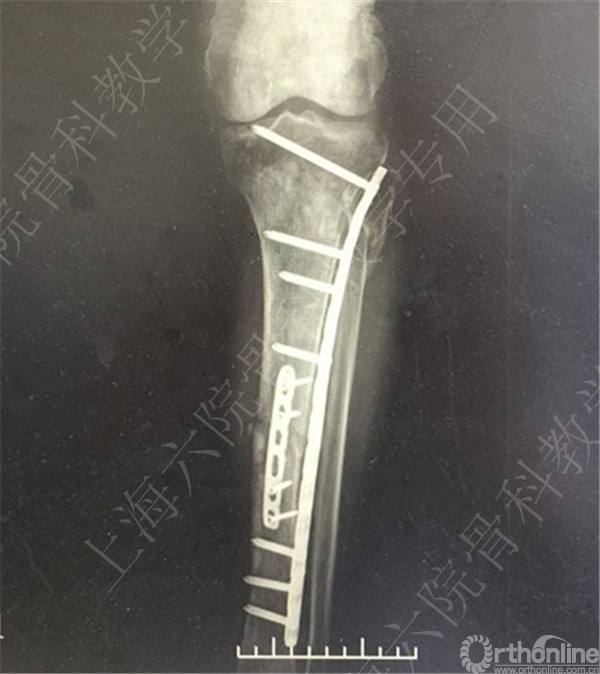

患者择期行左胫骨切开复位内固定术+髂骨异体骨植骨。

术后X线摄片示:骨折对位对线可,内固定牢靠,左胫骨对线可。